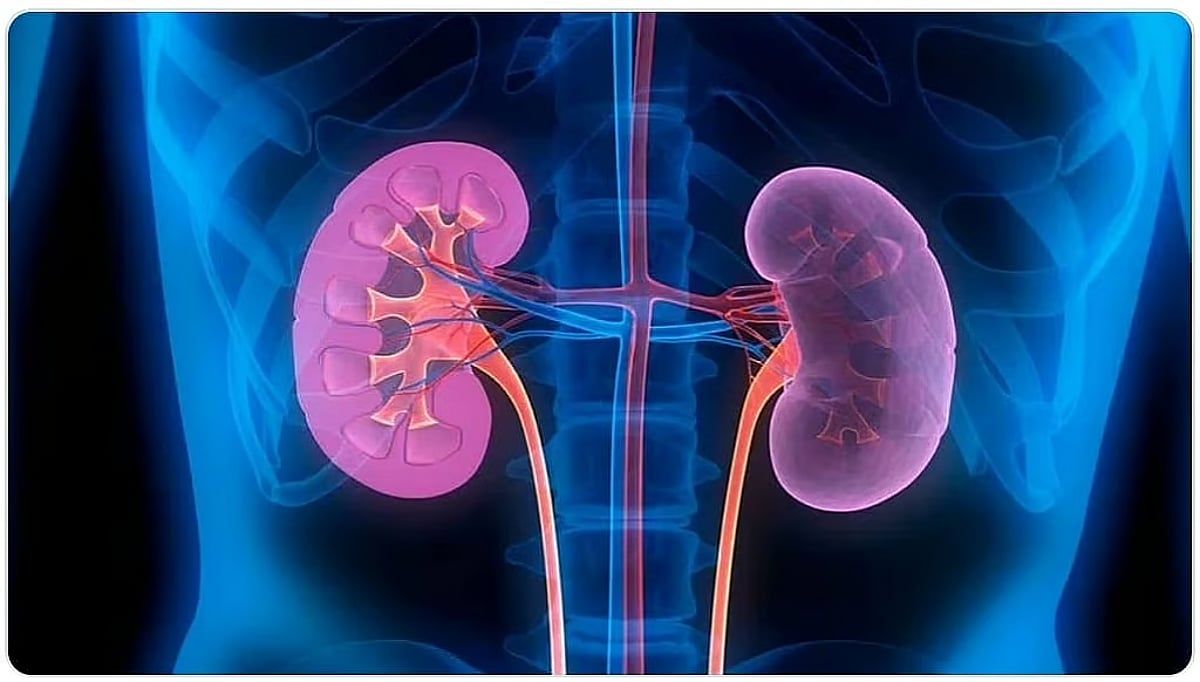

وقال مستشفى أجياد الطوارئ في إنفوجراف توضيحي نشره عبر حسابه الرسمي على منصة "إكس" إن طرق الوقاية من حصى الكلى تتمثل في:

- شرب كميات كافية من الماء كل يوم ما بين 8 إلى 12 كوباً لتجنب التعرض للجفاف.

- الاهتمام بشرب السوائل عند ممارسة التمارين.

- تجنب المشروبات الغازية.

- التقليل من أكل الملح.